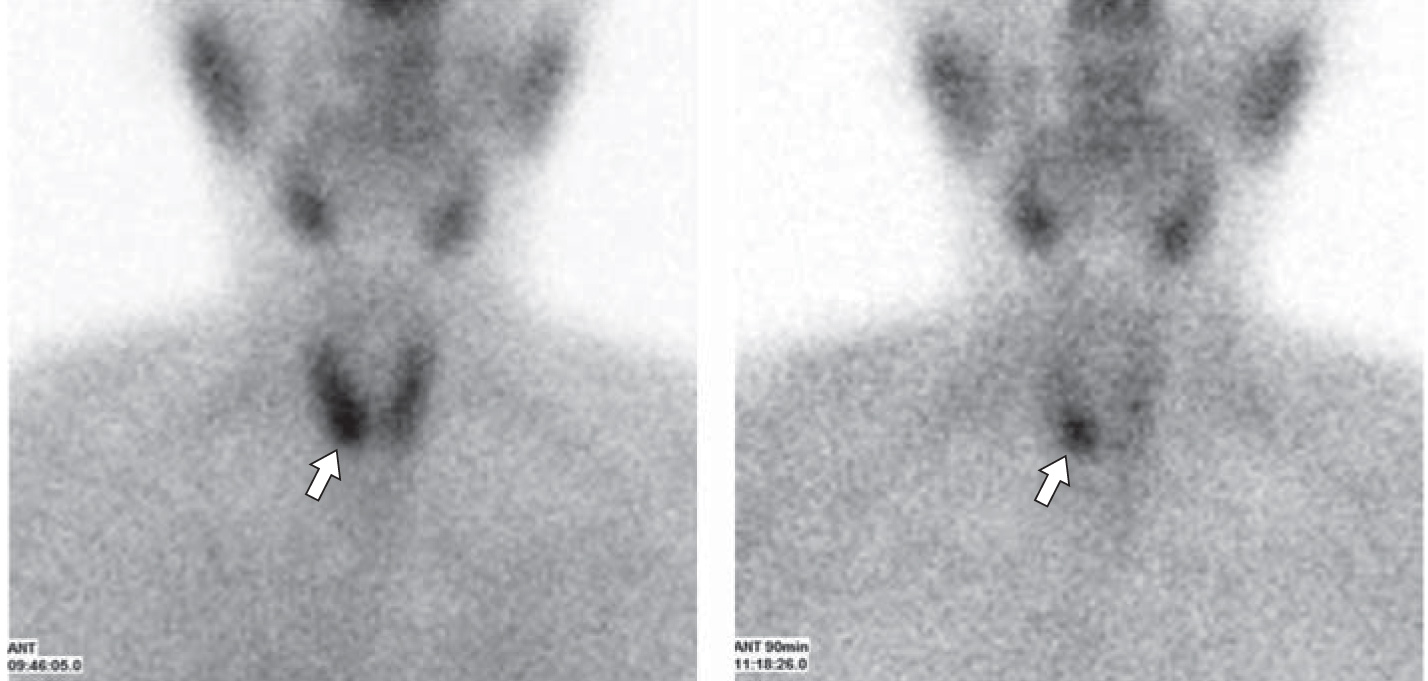

4. Fig. 3. a - the formation of the thyroid gland (arrow); b - with increased blood flow after intravenous administration of ultrasound contrast SonoVue (arrow) (images Soldatova T.V., Research Center for Endocrinology). | |

6. Fig. 5. Two-phase scintigraphy. An early and delayed scan with 99mTc-MIBI, the formation of the thyroid gland in the projection of the right lobe of the thyroid gland (arrows) is visualized, preserving the increased capture of the radiopharmaceutical (images of M. Degtyarev, Research Center for Endocrinology). | |